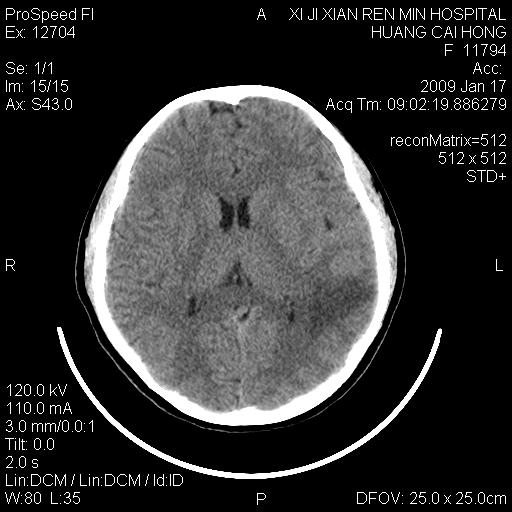

以下是引用zbp537在2009-1-19 13:54:00的发言:[br]首先考虑脑炎。[br]诊断依据:[br]1、患者较年轻。[br]2、有感冒病史。[br]3、左侧颞枕叶这么大一片低密度影,占位征象却不明显,不符合肿瘤特征,其内的高密度影为出血灶。

以下是引用xiaoniu在2009-1-19 13:29:00的发言:[br]左侧颞叶三角形低密度影,占位效应不明显,其内点片样高密都影,青少年患者,首先考虑:少突胶质瘤。因为有感冒病史,不能除外感染的可能。